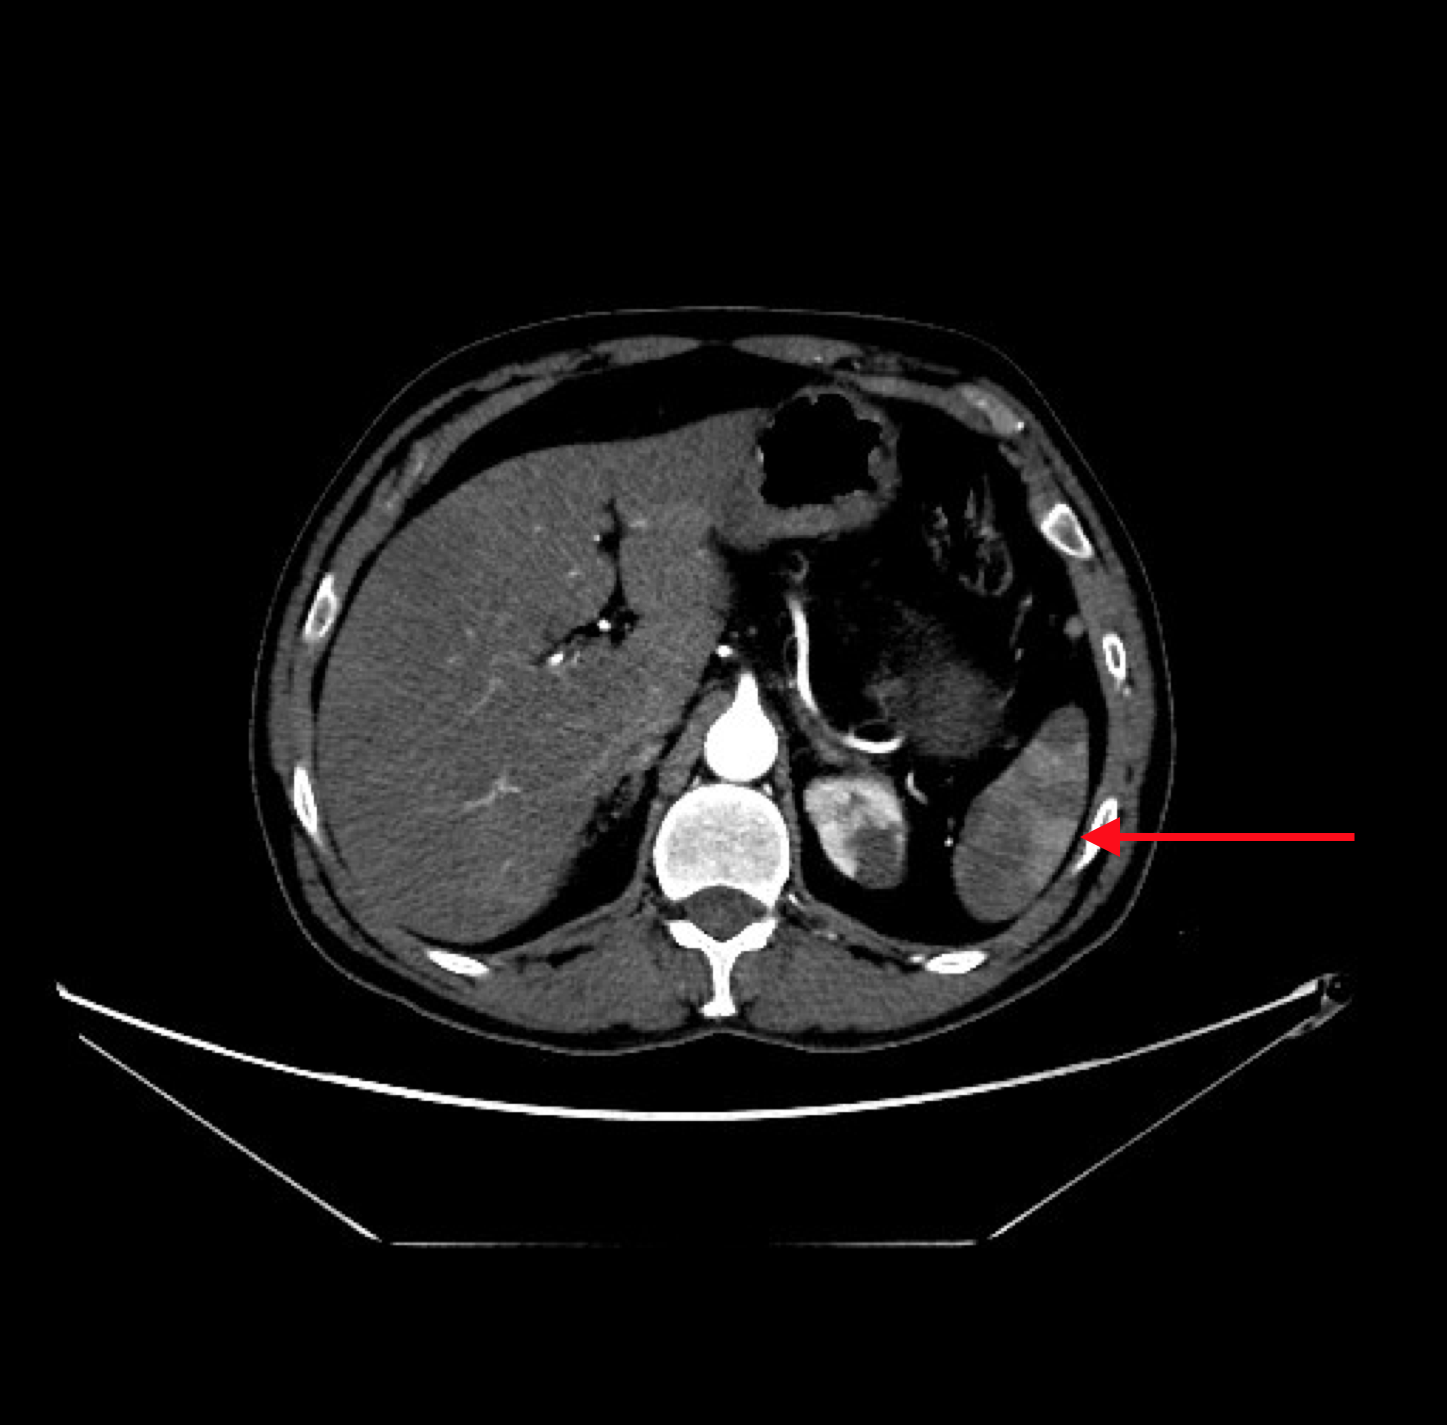

The CT angiogram and CT chest aortogram revealed a hypodense filling defect in the aorta below the level of the renal arteries causing partial occlusion of the aorta (Figure 2). There was complete occlusion of the left common iliac artery just after bifurcation of aorta extending up to the common femoral artery (Figure 3). There was good contrast uptake in right common iliac artery, femoral artery, superficial femoral artery up to the popliteal artery then the abrupt cut off of right popliteal artery present with no contrast filling seen in the distal arteries (Figure 4 and 5). Additionally, multiple bilateral wedge shaped infarcts seen in both the kidneys and the spleen (Figures 6). Chest x-ray was normal.

Figure 6:CT Aortogram revealing multiple infarcts in the spleen in transverse section.